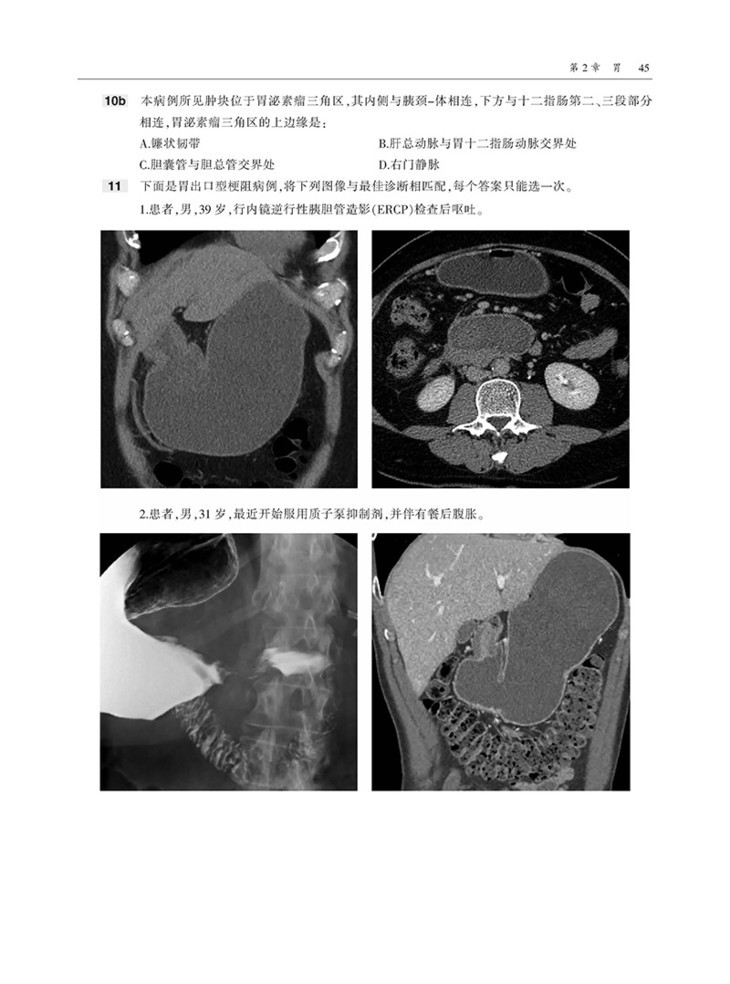

本书内容采用问答体例,首先给出患者病史和影像图片,然后列出问题和选项,便于读者独立思考,选择答案。各章末附有选择题答案和解析,正确选项和错误选项均有详细的注释,有助于读者加深理解和记忆。

300余道选择题,每道问题均附有答案、解析和参考文献,便于读者自查知识点、快速理解和记忆。

囊括数百幅高清图像,直观显示病变的形态与特点等。